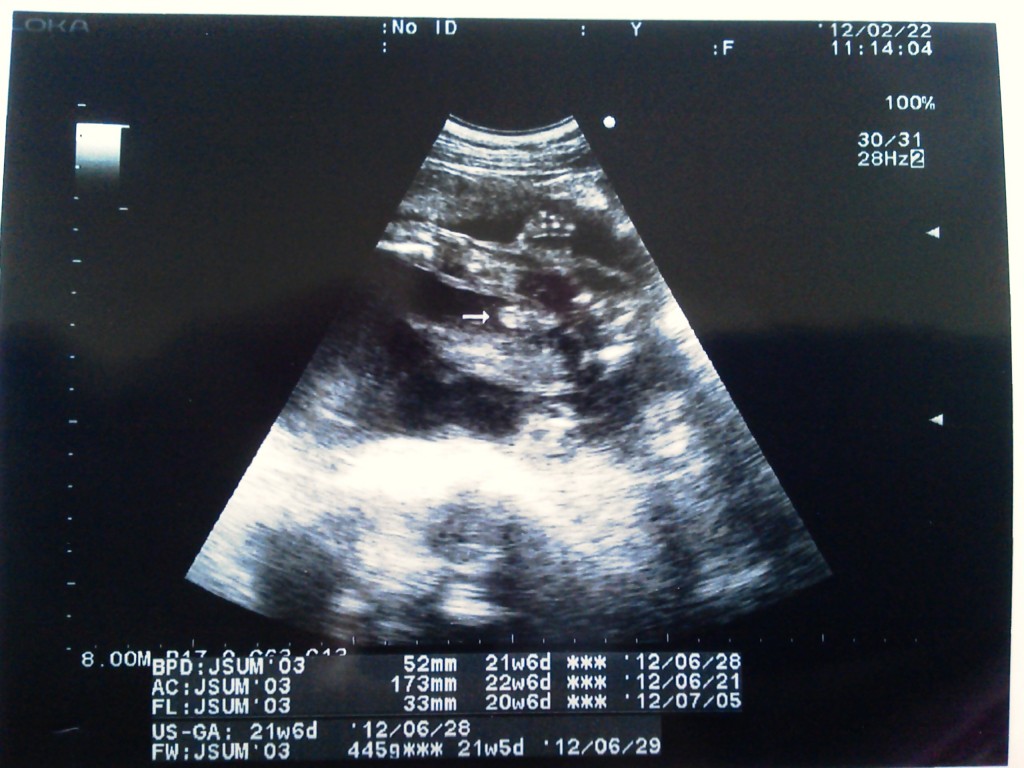

Mar 30, 15 · 8週~11週 15~mm;ママライターのみなさんの妊娠出産体験談から妊娠21週の赤ちゃんのエコー写真を集めました。 医師監修妊娠21週の週数別情報 Tomomiさんの妊娠21週目のエコー写真 娘ちゃん、頭が大きい!健康診査の中では、妊娠23週までの間に2回、妊娠24週から35週までの間に1 回、36週以降に1回実施することとされています(11)。 11)・ 平成21年2月27日雇児母発第号「妊婦健康診査の実施について」

May 13, 11 · BPD64mm(予定日より3W5D早い)APTD66mm(予定日より4W3D早い)FL36mm(予定日通り)体重679g主治医は元気な赤ちゃんですよ、と言うのですが単に頭が妊娠21週0日の胎児の大きさ/体重262g~512g(*) 妊娠19~週ごろまでは赤ちゃんの脳の表面にはシワがなく、ツルツルしています。 妊娠21週ころになると、初めてシワが登場してきます。 シワができると、脳の表面積は広がり、脳の働きを担う脳細胞の数も増えていきます。 さらに、妊娠24週(妊娠7ヶ月の最初の週)に入ると、人間特有の大脳新皮質の形がNov 24, 05 · そこで、頭の大きい赤ちゃんをご出産されたお母さんにぜひ教えていただきたいのです。 妊娠35週の頃の赤ちゃんの頭囲(BPD)はどれくらいだったでしょうか? わたしの胎児は現在FL=64mm、FTA=713cm2、BPD=963mmです。どんなものでしょうか・・・?

今日の赤ちゃんです! 二人目妊娠で11週3日です。 流産経験ありで5センチの子宮筋腫持ちの為まだまだ不安ですが1日1日大切に大事に育てたいと思います。 6週辺りから全く出血も腹痛もなく今日の検診では赤ちゃんは既に5㎝に!Mar 11, 15 · 体重 発達 約25cm 300〜450g ・脳が急成長 ・生殖器が形成されていく ・寝たり起きたりする 妊娠21週の赤ちゃんは、身長25cm、体重300g~450g程度の大きさに成長しています。 脳の急成長が起こる時期で、聴覚も記憶力も発達しています。 逆子はまだ心配しなくても大丈夫。 妊娠21週目の胎動の様子Jan 29, 21 · 21週の赤ちゃん 成長具合は? 全身に脂肪がついて体は丸みを帯び、赤ちゃんらしいバランスの体形になります。 髪の毛が生えたのが超音波検査でわかることもあります。 赤ちゃんが動いた! 胎動を感じる時期 21週ごろは、感じ方には違いがありますが、ほとんどのママが赤ちゃんの動きを感じるようになります。 胎動を感じて初めておなかの赤ちゃんの存在を

Dec 14, 15 · 妊娠21週&22週目の胎児(赤ちゃん)の大きさ 子宮の大きさは、大人の頭の大きさを上回り、おへその上くらいまでの大きさになっているそうです。妊娠4カ月 受精から77日~日目 胎児の大きさ 頭殿長(座高)が75mm 体重はgほど 妊娠13週(13w)の赤ちゃんは、腕が伸びてきて、生まれたときに近いバランスのとれた体つきになってきます。 足もこれからどんどん伸びてきます。 超音波検査でも全体が一番見える時期なので、夫婦2人で妊婦健診に行くのもおすすめです。 <妊娠13週目 目次>Apr 22, 21 · 妊娠21週目 妊娠21週目の赤ちゃんの成長 心臓の鼓動: 赤ちゃんの心臓の鼓動が聴診器で聞こえるほど大きくなってきましたが、ママの心臓の音と区別するのは難しいかもしれません。 そんな時は 早いほうの心臓の音を聞いてみてください。 赤ちゃんの心拍数は1分間に1~160回ほどで、成人の心拍数の約2倍です。 妊娠中の多くのママによると、赤ちゃんの心臓の